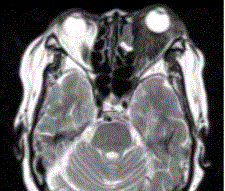

问题 患者女,64岁,左眼突出5年余。查体左眼球前突6mm,眼球运动自如,眼底无异常,下睑扪及边界不清、质软的肿块,视力正常,MR表现如下图。 经抗生素及激素治疗后好转,则诊断支持

选项 A.炎性假瘤 B.眼型Grave病 C.黑色素瘤 D.转移瘤 E.眼眶海绵状血管瘤 F.弥漫型淋巴管瘤

答案 A